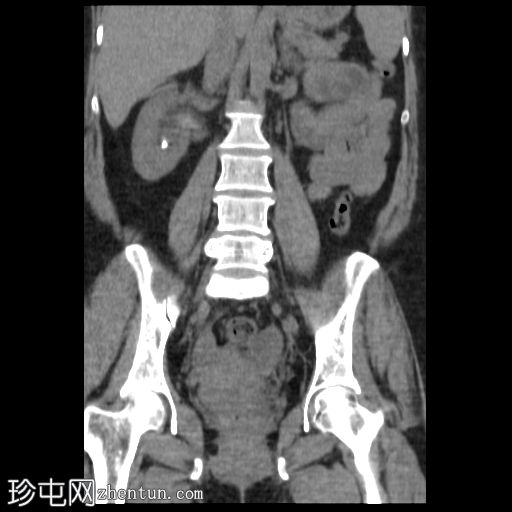

3.jpg

矢状位

平扫

平扫CT显示右肾盂内有一结石,大小约17 × 16 mm,CT值1115 HU,引起轻度肾积水。右肾下盏内可见另一小结石,大小约8 × 4 mm,CT值611 HU。

子宫前壁可见一软组织肿块,大小29 × 24 mm,与子宫肌层密度相近,呈外生性生长,无钙化或脂肪成分。

非增强 CT 对检测泌尿系统结石具有很高的敏感性。大多数结石为放射性不透光结石,其衰减值因成分而异。本例中,较大的右肾盂结石的衰减值为 1115 HU,符合鸟粪石的特征,鸟粪石通常与感染有关,在女性中更为常见,并且可能形成鹿角状结石。

较小的下肾盏结石的衰减值为 611 HU,提示为草酸钙结石。识别结石成分对于指导治疗和预防具有重要的临床意义。

关于子宫病变,其主要符合浆膜下肌瘤的特征。建议进行经阴道超声检查。